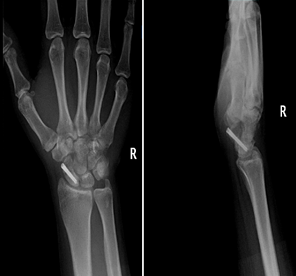

Röntgen: İlk gün çekilen röntgende kırık hattı bazen görülmez. Eğer şüphe varsa hasta 7-10 gün sonra tekrar röntgene çağrılır. En güzeli MR veya BT çektirilir.

BT ve MR: Şüpheli durumlarda veya kırığın yer değiştirmesini (deplasman) görmek için Bilgisayarlı Tomografi (BT) en net sonucu verir. Manyetik Rezonans (MR) ise kemiğin kanlanmasını ve ödemi gösterir.

skafoidröntgen